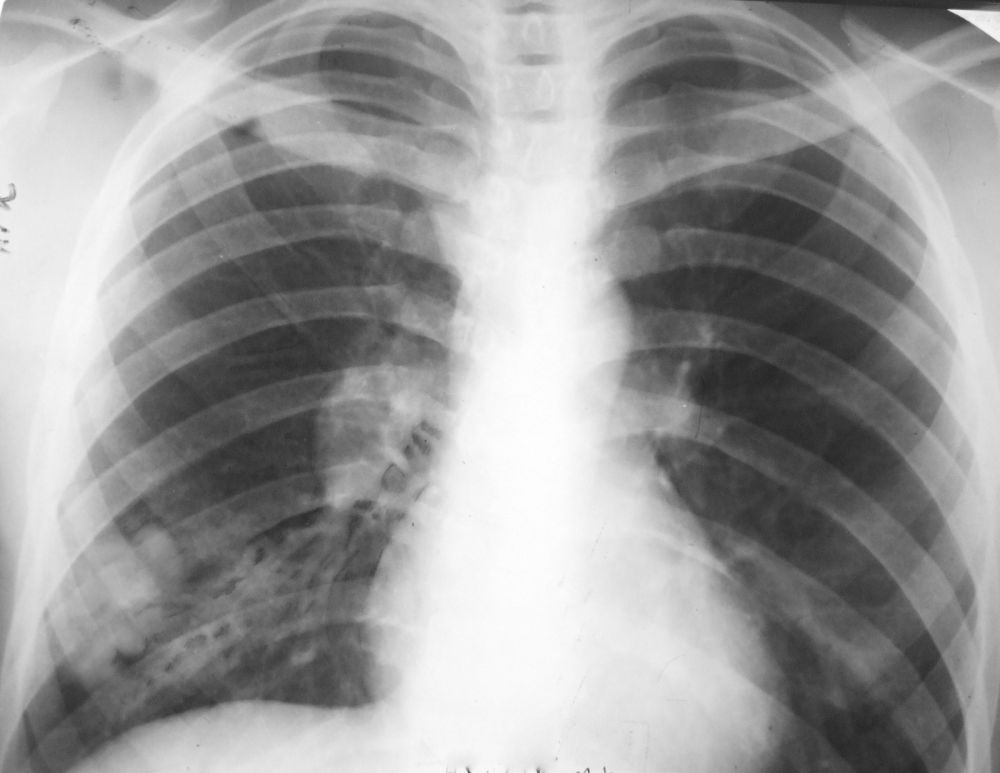

Фтизиатр о туберкулезе и маршрутизации пациентов Херсонщины в другие регионы России24 марта, во Всемирный день борьбы с туберкулезом, главный врач «Фтизиопульмонологического центра» Херсонской области Любовь Бондарь рассказала о заболевании и группах...

О его профилактике и выявлении рассказала главный врач ГБУЗ “Фтизиопульмонологический центр” Любовь Бондарь. Туберкулёз – это инфекционное заболевание, которое вызывается микробактериями. Их открыл Роберт Кох в 1882 году....